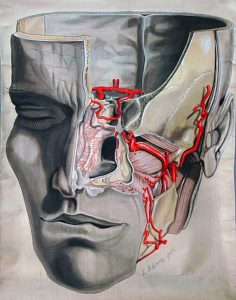

La arteria maxilar interna es una de las dos ramas terminales de la arteria carótida externa. Esta, a su vez, es una de las ramas terminales de la arteria carótida común. Conocida simplemente como arteria maxilar, nace a nivel del cuello del hueso mandibular y tiene un recorrido horizontal y un poco ascendente.

La arteria maxilar aporta muchas ramas de irrigación para los planos profundos de los músculos de la cara. Para la simplificación de su estudio anatómico y quirúrgico, la arteria se divide en tres porciones que están determinadas por su relación con el músculo pterigoideo lateral.

Desde el inicio de su recorrido en la articulación temporo-mandibular, la arteria maxilar entra en la fosa infratemporal del cráneo, un área está formada por los huesos esfenoides, maxilar, temporal y mandibular.

Luego continúa su trayecto hacia la fosa pterigopalatina, donde se relaciona con el músculo pterigoideo lateral, siguiendo un recorrido paralelo a él.

Dado que esta arteria aporta una cantidad considerable de ramas colaterales, se divide su recorrido en tres segmentos para simplificar su estudio anatómico.

Esta división se hace según la relación de la arteria con el músculo pterigoideo lateral. Así, se encuentran los siguientes segmentos:

– Segmento 1: también conocido como segmento óseo. Se ubica en el cuello de la mandíbula. En este pequeño trayecto la arteria da cinco ramas que se encargan de nutrir estructuras internas del cráneo.

– Segmento 2: denominado segmento muscular debido a que en esta parte sigue paralelamente al músculo pterigoideo lateral. Esta sección da cuatro ramos vasculares a estructuras bucales y también es la principal irrigación del músculo pterigoideo lateral.

– Segmento 3: llamado segmento pterigopalatino, es la porción que se encuentra anterior al músculo pterigoideo lateral y da ocho ramos vasculares que se encargan de irrigar el paladar, los músculos de la masticación y la región infraorbitaria.

La arteria maxilar se encarga de irrigar estructuras vecinas de la cara y el cráneo, a través de sus múltiples vasos colaterales.

Estas ramas nutren estructuras tan importantes como la glándula parótida, los músculos de la masticación, las estructuras bucales, nervios craneales e incluso las meninges.

Varias de las ramas colaterales de la arteria maxilar se encargan de irrigar los órganos de los sentidos, incluyendo la mucosa nasal y la región orbitaria que da pequeños ramos a los ojos.

También otorga múltiples ramas colaterales que viajan dentro del cráneo y nutren algunos nervios de la base del mismo.